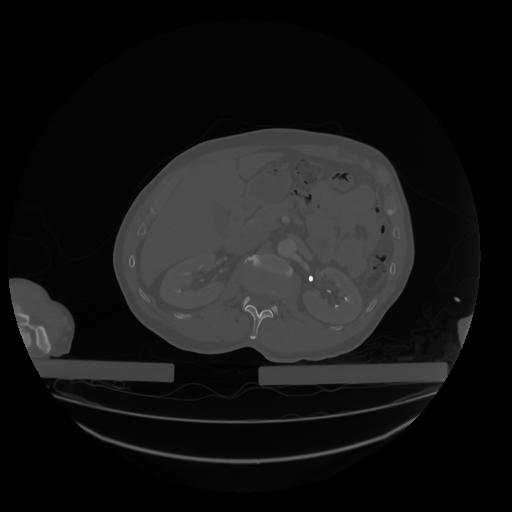

28 CUERPO,CE,Vol,2.0,CUERPO,,